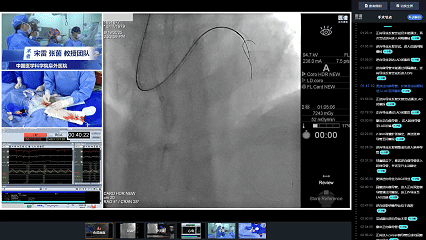

全景手术复盘

手术过程

结合全景手术复盘,张茵教授详细阐述CTO PCI操作技巧与策略思考:

➤逆向策略时机选择

若正向导丝尝试失败,如开口闭塞导致正向通过不可行,可直接启动逆向策略。一些特殊情况如近端纤维帽不清晰而逆向条件良好;远端纤维帽处存在大分叉病变等,可尽早启动逆向策略。若正向导丝失败后的长段闭塞≥20mm,血管严重迂曲、钙化,无大的分支,可使用R-CART技术。